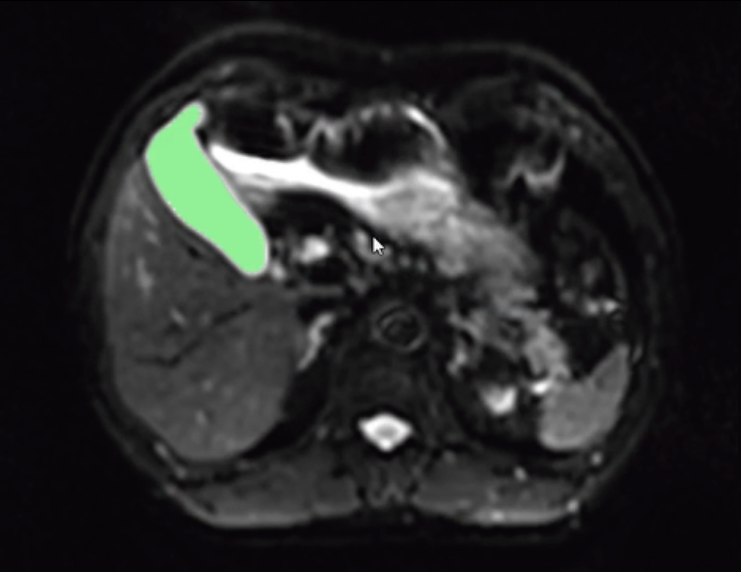

在宣传影片中,影为医疗工程师通过自主研发的计算机软件Medraw系统,将患者的二维平片转化为三维视图:

我们利用MRI增强序列显示胰腺及病灶边界,可以清晰看到胰腺的钩突、胰头、胰颈、胰体和胰尾。

利用MRCP序列勾画胰胆管,显示肝内胆管、肝总管、胆囊、胆囊管、胆总管主胰管